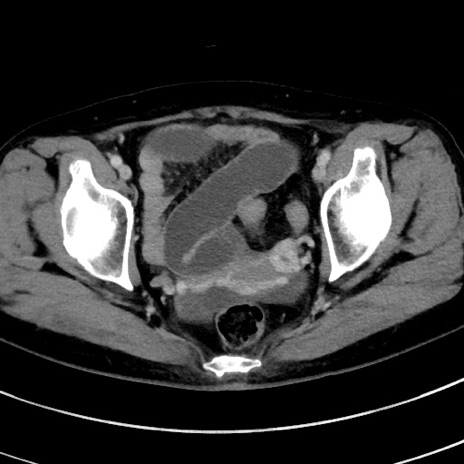

症例

冠状断像